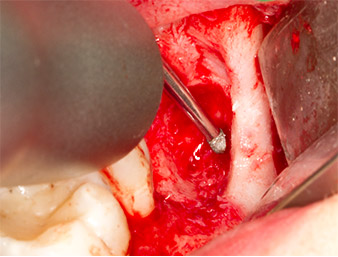

Dopo l'anestesia tronculare e l'anestesia locale, il sito operatorio è stato aperto e il tessuto molle esposto per l'accesso retromolare boccale (Fig. 3).

Il tessuto al di sopra del residuo di radice non era completamente ossificato ed era costituito per la maggior parte da tessuto di granulazione modificato dall'infiammazione (Fig. 4).